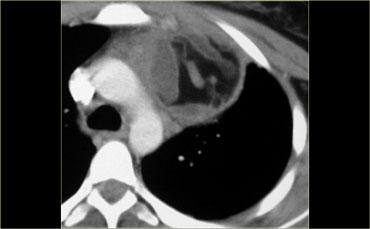

Hãy mô tả hình ảnh.

Sau đó tiếp tục.

Đầu tiên, lưu ý tuyến ức lớn ở trẻ nhỏ này.

Ngoài ra còn có một khối ngấm thuốc ở trung thất sau lan vào ống sống.

Đây là hình ảnh điển hình của u mạch máu (hemangioma).